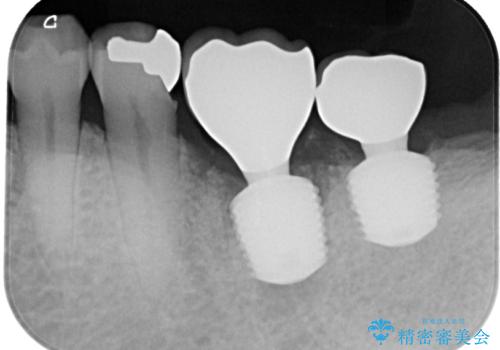

咬合力で破折した奥歯 抜歯即時インプラントで短期間治療

- 以前、咬合力の強さで歯の神経が失活してしまい、当院にて根管治療を行った患者様ですが、今度は咬合力の影響で歯根が破折してしまった患者様です。

歯根が破折してしまった歯は抜歯が必要となり、特に咬合力が強い方ですと、インプラント治療による治療がお勧めとなります。

従来のインプラント治療ですと、抜歯をしてからその部分の骨が回復するまで数か月待機し、その後インプラント埋入、生着を待って土台の頭出し手術、仮歯の装着となるため、咬合回復するまでに半年かそれ以上の期間が必要となってしまいます。

咬合力の影響で歯が壊れてしまう方の場合、長期間欠損が続くと、連鎖するように他の歯が壊されてしまうリスクがあるため、抜歯即時インプラントにより、治療期間の短縮を図ることとしました。